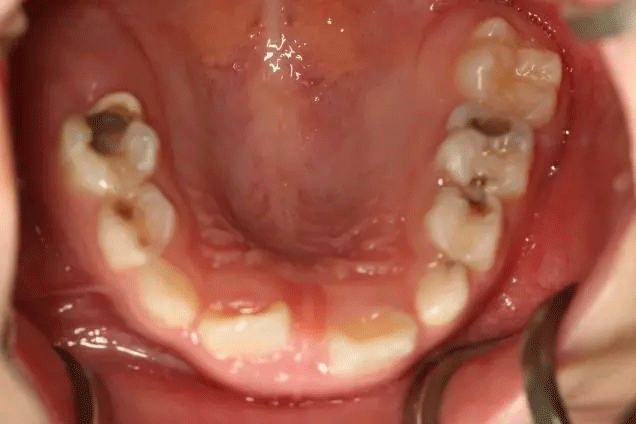

孩子1歲開始已經(jīng)出現(xiàn)齲齒

但是媽媽2年后才帶孩子就診

這時(shí),孩子已經(jīng)斷斷續(xù)續(xù)疼了3年

有些牙齒都已經(jīng)爛得很嚴(yán)重了

甚至牙齒幾乎都爛光僅剩下牙根